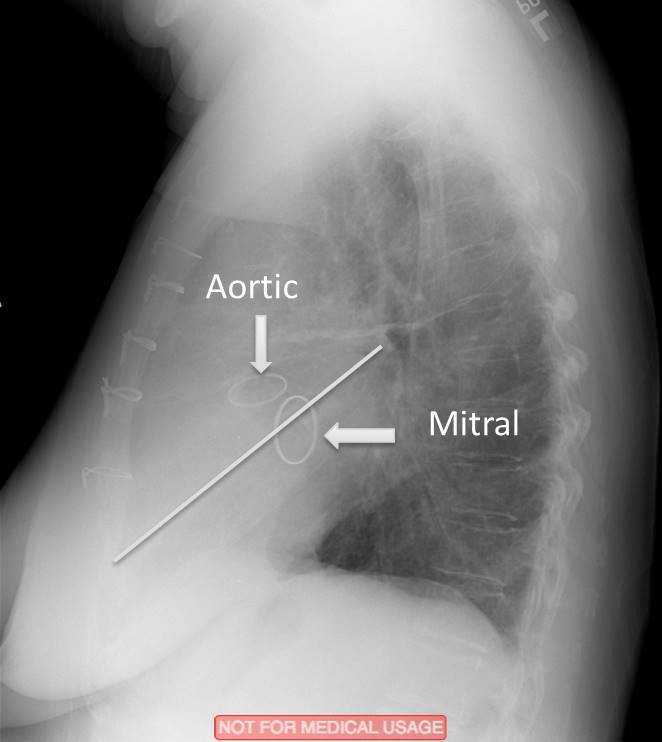

What are the indicated valves?

What valves are indicated?